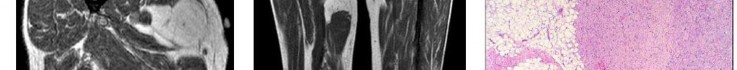

A 15-year-old male presents with deep knee pain awakening him at night. Radiographs show a permeative destructive lesion in the distal femoral metaphysis with a 'sunburst' periosteal reaction and Codman's triangle.

Biopsy confirms high-grade conventional osteosarcoma. What is the most critical prognostic factor for long-term overall survival in this patient?

Explanation

For localized high-grade osteosarcoma, the most important prognostic indicator is the histologic response to neoadjuvant chemotherapy. This is evaluated during the definitive resection. A 'good response' is typically defined as greater than 90% or 99% tumor necrosis. Patients who achieve this level of necrosis have a significantly improved disease-free and overall survival rate compared to 'poor responders' who have extensive viable tumor cells remaining.